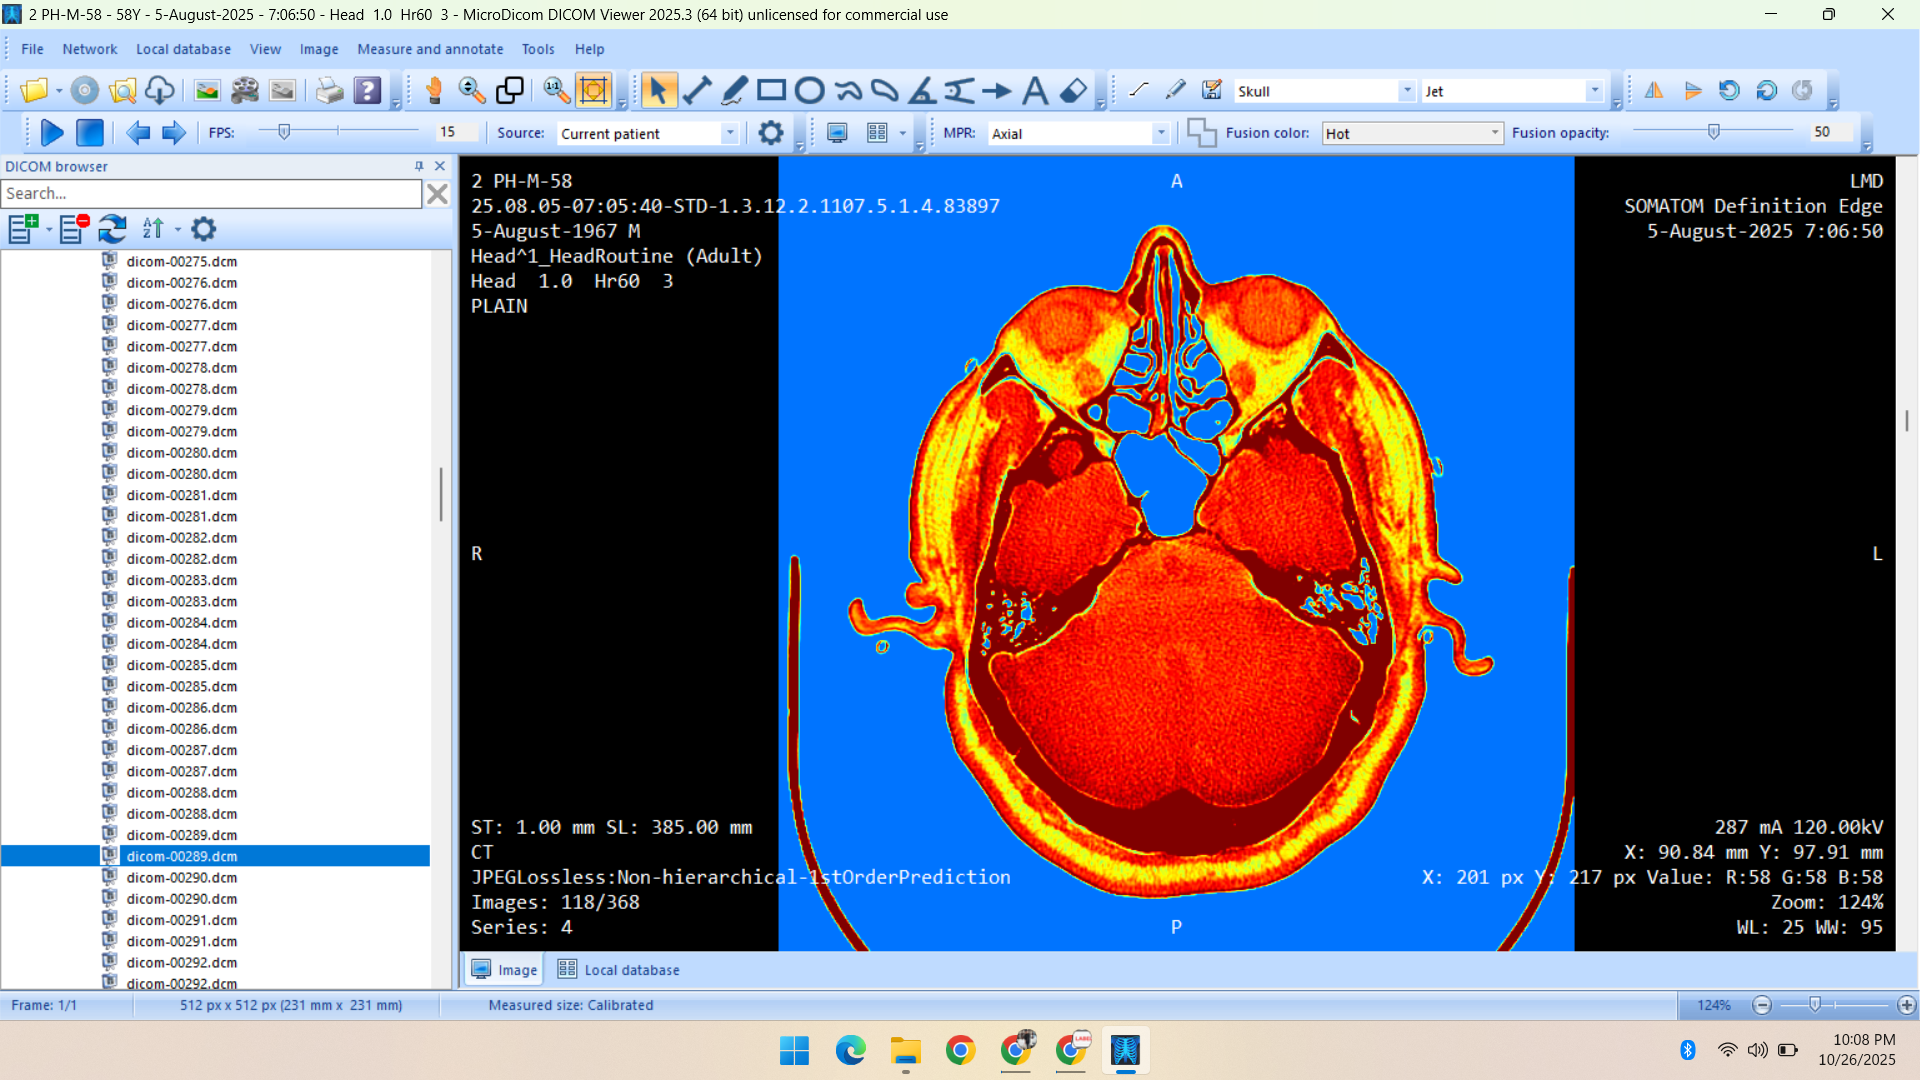

- Radiology Data – CT Scans, X-Rays, MRI, Echocardiography, Ultrasound.

Deep specialization in radiology, pathology, and histopathology datasets, annotated with medical precision.

Healthcare & Medical Data Supply

We specialize in healthcare datasets including radiology (CT, X-ray, MRI, Ultrasound, Echocardiography), pathology microscopy, and histopathology images — all ethically sourced and research-ready.

- CT Scan